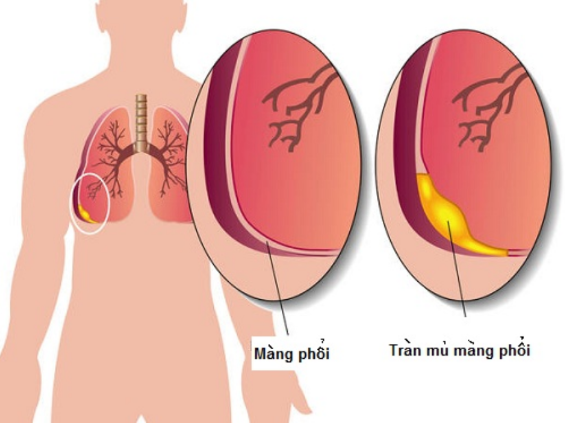

Tràn mủ màng phổi ở trẻ em: Nguyên nhân, triệu chứng và cách điều trị

SKĐS - Tình trạng tràn mủ màng phổi thường gặp ở trẻ em, nhất là ở trẻ bị viêm phổi. Nếu không điều trị đúng và kịp thời có thể gây tình trạng suy hô hấp, dày dính màng phổi và có thể dẫn đến sốc nhiễm trùng.

2. Dấu hiệu nhận biết tràn mủ màng phổi

Thông thường khi bé bị tràn mủ màng phổi có các biểu hiện cơ bản là sốt dai dẳng, lười ăn, mệt mỏi… Kèm theo ho, khó thở… và đa số trẻ đều bị viêm nhiễm đường hô hấp, viêm phổi, nhiễm trùng da, viêm cơ trước đó. Theo nghiên cứu, khoảng 90% các bệnh nhân bị viêm mủ màng phổi khởi đầu bằng biểu hiện ho và sốt, giống như trong các bệnh nhiễm khuẩn hô hấp thông thường. Chính vì thế cha mẹ thường chủ quan và những triệu chứng không điển hình này cũng dễ dẫn đến chẩn đoán bệnh ở giai đoạn khó khăn. Thực tế tại phòng khám, nhiều bệnh nhi nhập viện trong tình trạng khoang màng phổi đã có rất nhiều mủ, gây khó khăn cho quá trình điều trị.

Dấu hiệu lâm sàng mà các bác sĩ phát hiện trẻ có triệu chứng tràn mủ màng phổi là các biểu hiện nhiễm trùng ( tổng trạng, vẻ mặt nhiễm trùng, nhiệt độ). Trẻ có thể sốt >38,5 độ C, nhịp tim, nhịp thở nhanh. Các biểu hiện tại phổi có thể nhận thấy là ho, đau ngực, thở nhanh. Quan sát thấy giảm di động lồng ngực một bên, giảm thông khí một bên, gõ đục. Chọc dịch khoang màng phổi có dịch mủ.

Kết quả xét nghiệm cho thấy số lượng bạch cầu tăng, CRP tăng, PCT tăng, Lactat tăng. Xquang mờ góc sườn hoành thường một bên, có thể mờ hoàn toàn một bên phổi, trung thất bị đẩy bên phía đối diện…

Triệu chứng tràn mủ màng phổi là các biểu hiện của nhiễm trùng

3. Chẩn đoán xác định tràn mủ màng phổi

4. Biến chứng tràn mủ màng phổi

Nếu trẻ bị tràn mủ màng phổi cần phải được chẩn đoán và điều trị sớm, điều này giúp tránh được biến chứng lâu dài như: Khả năng giãn nở của phổi và chức năng hô hấp của trẻ.

Các biến chứng có thể gặp là rò khí quản - màng phổi, áp xe phổi, viêm mủ màng ngoài tim… Ngoài ra, trẻ có thể gặp các biến chứng viêm xương sườn, vẹo cột sống tạm thời, nhiễm khuẩn huyết…